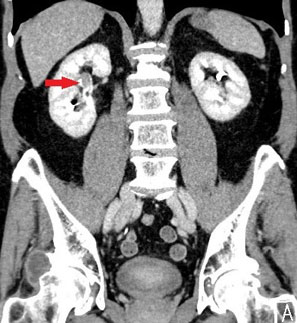

| Computertomografie-Bild mit Nierenbeckenkrebs rechts |

Abbildung 3: Spezielle Computertomografie mit Darstellung eines Nierenbeckenkrebs im oberen Teil des Nierenbecken